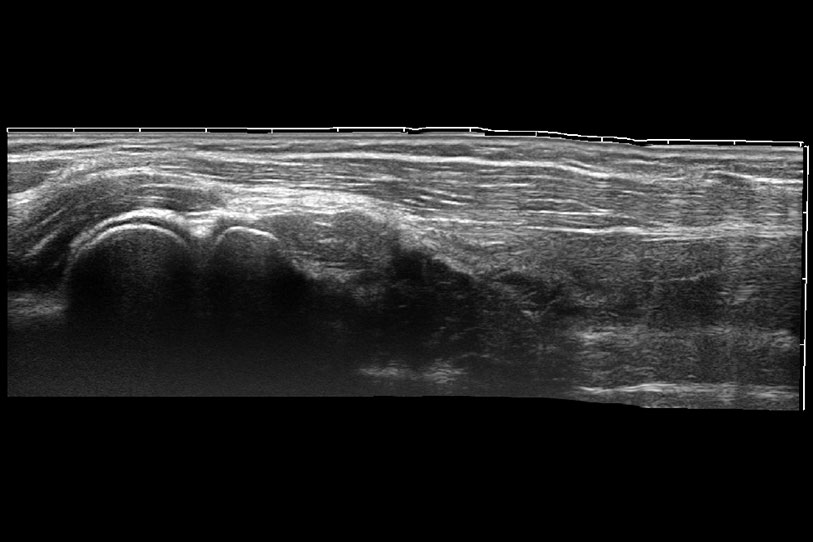

ProPet 70 進一步提升了微米成像算法,更加注重對基礎(chǔ)原始圖像的還原和保留,在有效減少斑點噪聲、增強組織邊界顯示的同時,避免過度優(yōu)化丟失真實的解剖信息。

通過色彩血流和實時寬景相結(jié)合,可觀察到完整的靜脈或動脈的血流,方便醫(yī)生檢查。實時掃查過程中,如有任何操作失誤也可以很容易地進行回掃擦除,而不會中斷掃查。

為精細結(jié)構(gòu)及組織邊緣提供高清晰度的圖像和更大的成像視野。幫助減輕醫(yī)生的用眼疲勞,快速精準獲得測量的數(shù)據(jù)。